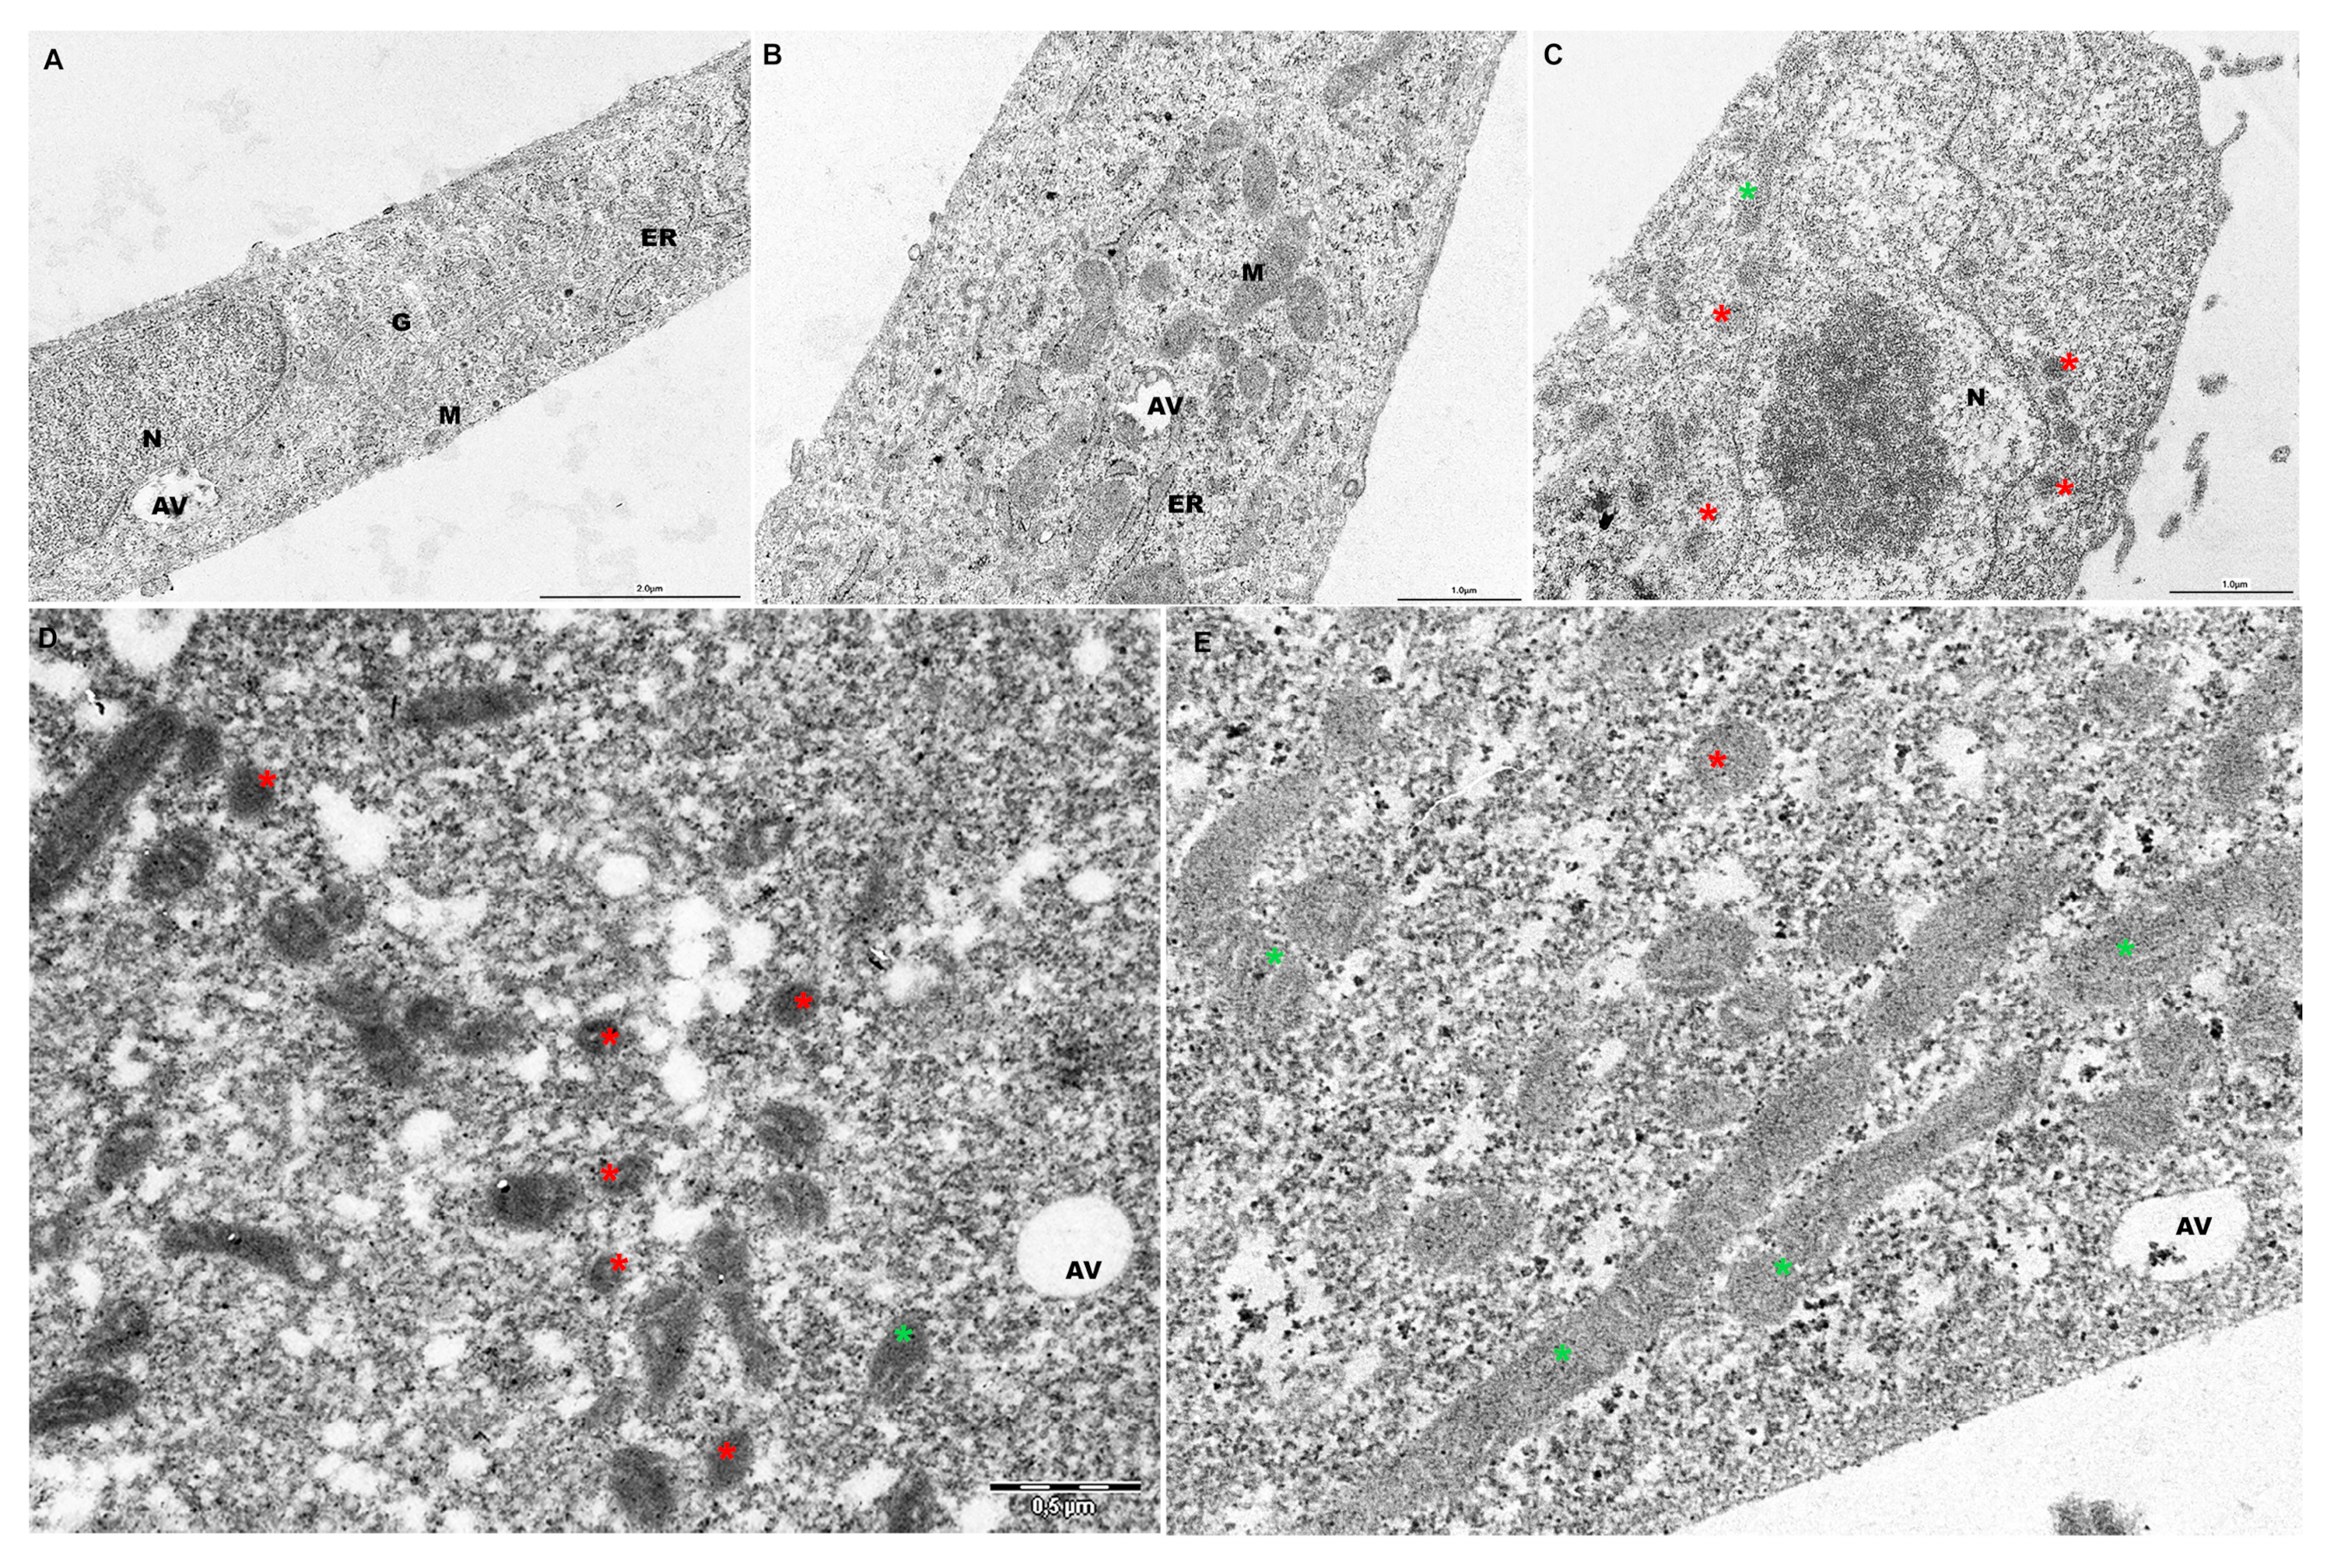

2.5. PF Preserves Mitochondrial Ultrastructure in ATO-Treated Cells

2.6. PF Reverses Mitochondrial Dysfunction Induced by Atorvastatin by Improving Mitochondrial Reshaping